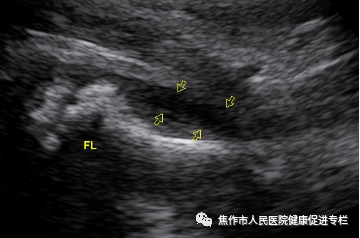

图3:左侧髋关节囊扩张,囊内股骨头周探及液性回声(黄色箭头)

绝大多数患儿表现为除关节囊增厚外,主要表现关节囊内积液,少数可伴滑膜增生。